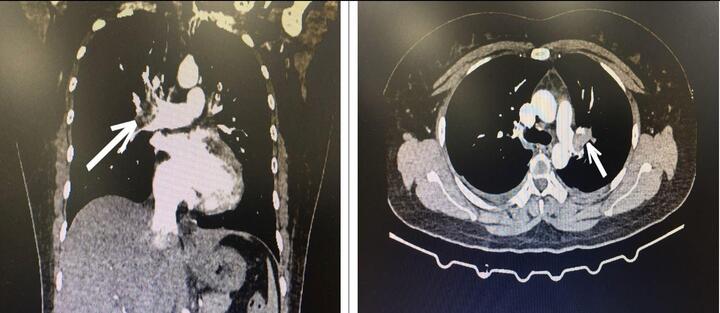

Bệnh nhân nhập viện trong tình trạng suy hô hấp, nguy kịch do huyết khối động mạch phổi hai bên gây hẹp, tắc mạch.